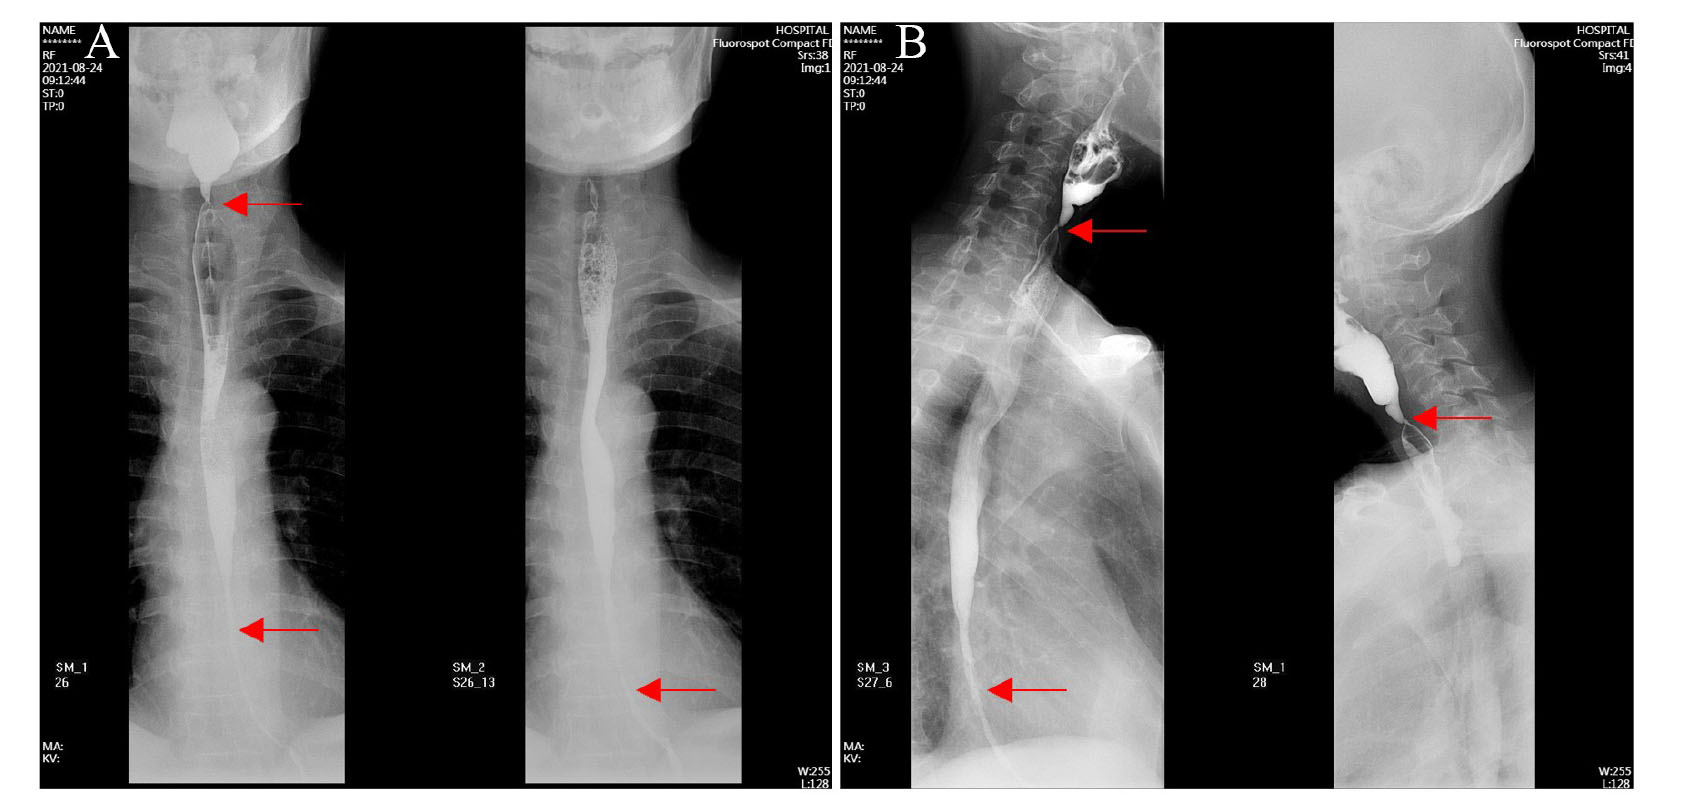

患者入院后于2021年8月24日行胃镜检查提示食管入口、食管中下段距门齿约30~40 cm处明显狭窄(图1A),予探条扩张后方能入镜至胃内,见胃窦变形,小弯侧大片溃疡形成,底覆白苔,周边黏膜充血水肿,幽门结构难以辨认(图1B),予球囊扩张(图1C),并放置鼻空肠管,术后第二天予肠内营养,但患者出现恶心、呕吐以及腹胀症状。2021年8月25日行上消化道碘剂造影显示食管上段、中下段狭窄,造影剂通过欠顺畅(图2);部分胃体、胃窦僵硬、狭窄并梗阻。心理科会诊提示患者有消极轻生念头,考虑为抑郁焦虑状态。经上述治疗后,患者肠内营养耐受情况欠佳,病情未见明显改善,梗阻仍然存在。经医务人员综合评估,确认该患者具有行PEG/J的适应证,无禁忌证。获得患方知情同意后,于2021年8月28日在气管插管全身麻醉下行PEG/J。患者取仰卧位,麻醉后经口插入胃镜,见食管仍狭窄,入镜至胃内,见胃腔变形,胃底较多胃液潴留,吸净后继续入镜至胃窦、幽门前区,见幽门仍狭窄,仔细辨认后送镜至十二指肠,见球部、降段黏膜光滑,退镜至胃体部,注气后于左上腹反复运用传统指压试验及透光试验寻找理想穿刺点,由于胃腔变形、胃移位,术者反复多次选点失败,后联合运用负压针吸试验,用含5 mL 生理盐水的注射器抽吸针筒保持负压,同时保证胃腔内充分注气,再次选定穿刺点后经腹部皮肤逐层缓慢穿刺至胃腔(图3A),最终定位于剑突下2 cm偏左约3 cm,消毒铺巾后,采用牵拉法完成胃造瘘术,并经胃造瘘管(管径6 mm)送入小肠管(管径3 mm)至空肠上段(图3B[5]。患者术中、术后生命体征平稳。于术后6 h开始向小肠管内注入少量营养液并逐量增加至正常管饲量,后逐渐过渡至日常食糜。经处理,患者病情及营养状况逐渐好转,于2021年9月25日出院。1个月后患者遵嘱返院复诊,监测体质量由住院期间最轻时39 kg增至47 kg,复查碘剂造影示食管上段狭窄较前减轻,中下段食管狭窄;胃窦部至幽门区明显狭窄伴梗阻,仅见少许造影剂通过幽门。医师与患方保持电话随访至撰稿日,得知患者呕吐次数逐渐减少至缓解,营养状况持续改善,造瘘管固定良好,造瘘口无红肿、渗液等(图3C)。

图2 一例上消化道严重腐蚀伤患者的上消化道碘剂造影图片

注:A为上消化道碘剂造影正位;B为上消化道碘剂造影斜位;箭头所示为食管上段、中下段狭窄处。